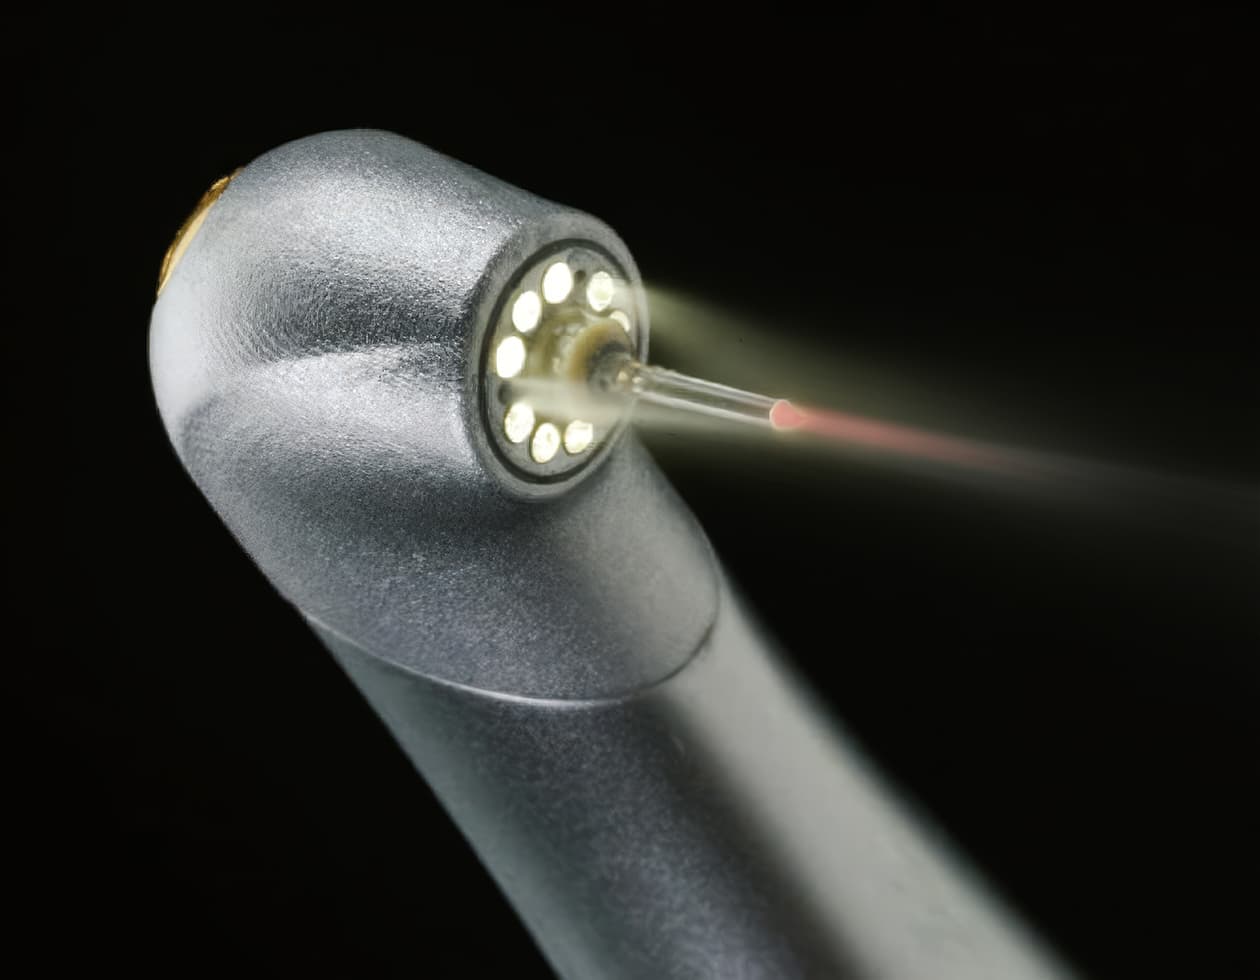

TU歯科のレーザー治療は、『より強く治療する方法』ではなく、

より精密で歯を保存することを重視したアプローチです。

レーザーは特定の部位を選択的に処置できるため、不要な損傷を抑え、回復の負担を軽減する目的で使用されます。

歯の保存を重視したアプローチ

必要な部位への精密なアプローチ

治療の安全性

周囲組織の損傷最小化

回復を考慮した設計

出血・腫れの軽減

審美的完成度の向上

歯肉ラインと笑顔の印象の精密化

レーザー治療が役立つ場合

レーザー治療は、既存のラミネート交換のように繊細な処置が必要な場合や

歯の損傷を最小限に抑え、回復の負担を減らしたい場合に役立ちます。